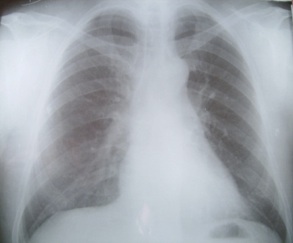

On notait une hyperleucocytose à 16600 /mm3 à polynucléose neutrophile ; un taux de protéine C réactive (CRP) à 100mg/l ; la gazométrie artérielle a montré une hypoxémie avec une pression artérielle en oxygène (PaO2) à 75 mm Hg et une hypercapnie avec une pression artérielle en gaz carbonique (PaCO2) à 50 mm Hg ; la recherche de BAAR dans les expectorations était négative. Un écouvillonnage nasopharyngé a été réalisé pour la recherche d’une infection à virus AH1N1. L’examen PCR H1N1 de l’écouvillonnage naso-pharyngé est revenu positif.Le traitement consistait en une oxygénothérapie par masque à haute concentration et à haut débit (10 litres/mn). Un traitement antiviral par oseltamivir (Tamiflu®) à la dose de un comprimé par jour a été débuté selon la recommandation du Ministère de la Santé Malgache. En outre nous avons ajouté une antibiothérapie par association d’Amoxicilline (4g/j) et de Metronidazole (1g/j). Une corticothérapie par Methylprednisolone (2mg/kg/j), un antipyrétique à base de Paracétamol (3g/j) et un diurétique de l’anse (40mg/j) ont été associé au Tamiflu®.L’évolution au 2ème jour d’hospitalisation est marquée par une défervescence thermique à 38°C, cependant persistait une polypnée avec sueur et cyanose des extrémités. La saturation périphérique était à 84% malgré l’oxygénation. Cette évolution a motivé d’une ventilation non invasive (VNI). Au 3ème jour d’hospitalisation ; on notait une amélioration de l’était ventilatoire marquée par une FR à 20 cycles/mn, une FC à 85 battements /mn, une SPO2 à 93% une apyrexie à 37° et une disparition de la cyanose des extrémités. Les gaz du sang était normaux (PaO2 à 95 mm Hg et PaCO2 à 38 mm Hg). L’examen PCR H1N1 a été positif. Nous avons arrêté progressivement la VNI et le patient a été mis en ventilation spontanée avec un débit d’oxygène à 3 litres par minute par sonde nasale. Après amélioration complète des paramètres pulmonaires, nous avons pu arrêter l’oxygénothérapie mais les autres traitements ont été poursuivis.Le malade était sorti de l’Hôpital le 07 décembre 2009 ; c’est à dire après 10 jours d’hospitalisation après constatation d’une guérison qui était confirmée par la radiographie pulmonaire (Figure 2). Il a pu reprendre ses activités quotidiennes en tant que médecin.